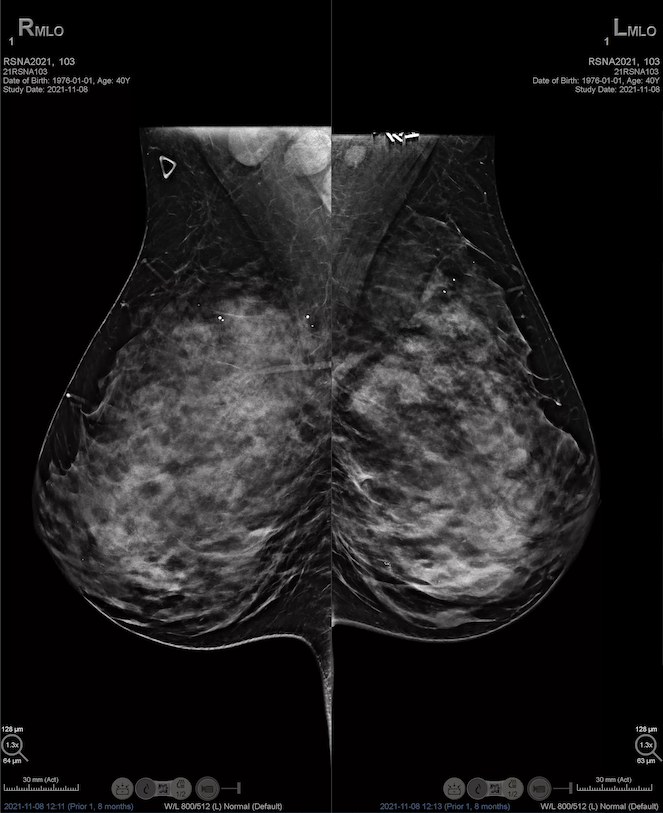

Klinik Güvenilirlik & Hologic Etkinliği

Hologic’in ileri teknolojilere dayanan sistemleri, klinik çalışmalarda güvenilirlik ve etkinlik açısından güçlü kanıtlar sunmaktadır. Büyük ölçekli bir retrospektif çalışmada (2013‑2023 arasında 184.006 tarama incelenmiştir), yüksek çözünürlüklü (High-Resolution, HR) tomosentez, standart çözünürlüklü taramaya kıyasla 1.000 kadın başına kanser tespit oranını 4.87’den 5.38’e çıkarmıştır. Bu artış, erken teşhis potansiyelini ciddi şekilde artırmaktadır.

Öte yandan, Hologic Clarity HD ile birlikte kullanılan Intelligent 2D ve diğer teknolojilerin klinik pratikte yalancı pozitif çağrı oranlarını düşürdüğü, görüntü netliğini artırdığı ve okuma sürelerini kısalttığı yönünde radyologlar tarafından olumlu geri bildirimler alınmıştır. Bu veriler, Hologic çözümlerinin tanı doğruluğu ile verimliliği dengeleyen ve güven veren bir altyapı sağladığını göstermektedir.